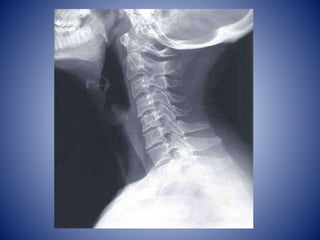

Vertebras Cervicales

• Las mas pequeñas de las vertebras

• Entre cráneo y tórax

• Orificio transversario ovalado: paso de arterias

vertebrales excepto C7 solo vena vertebral

accesoria

• Apófisis transversas: tubérculo anterior y

posterior

• C1 y C2 son atípicas

Atlas

• C1 es un hueso anular, vertebra + ancha

• Soporta el cráneo a través de la articulación

con sus cóndilos

• Carece de apófisis espinosa y cuerpo

• Formado por arco anterior y posterior con un

tubérculo y una masa lateral

• El arco posterior tiene un surco para la A.

Vertebral en cara superior también para el 1º

nervio cervical

AXIS

• C2 es la mas robusta de todas las vertebras

cervicales

• 2 caras planas y grandes: carillas articulares

superiores para el atlas

• Diente: apófisis odontoides, se mantiene en

posición por el ligamento transverso del atlas

• Apófisis espinosa bífida amplia

• Articulación sinovial en pivote